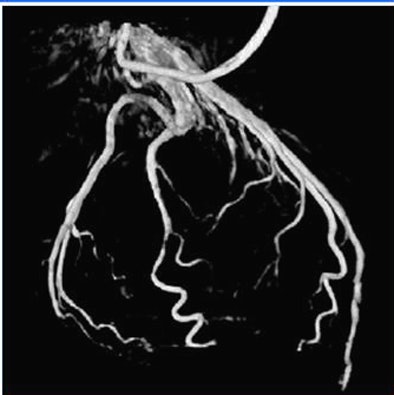

![]() |

| Vessel centerlines are detected using a multiscale, curvature-based "vesselness" filter with subsequent directional maxima detection and hysteresis thresholding. Minima of inconsistency measurements are performed over all cardiac phases to select the optimum reconstruction phases. From each centerline map, a squared-distance transform is calculated by pixel-wise squaring a chamber-distance transform. The squared-distance transforms are then back projected onto a reconstruction volume to receive a volume-distance transform, in which points with the shortest mean-squared distance to the centerline in the angiograms have minimum value. The normalized minimum-value forward projections are then calculated and integrated over the vessel centerlines, yielding a number; the lowest numbers represent angiograms belonging to similar motion states. |